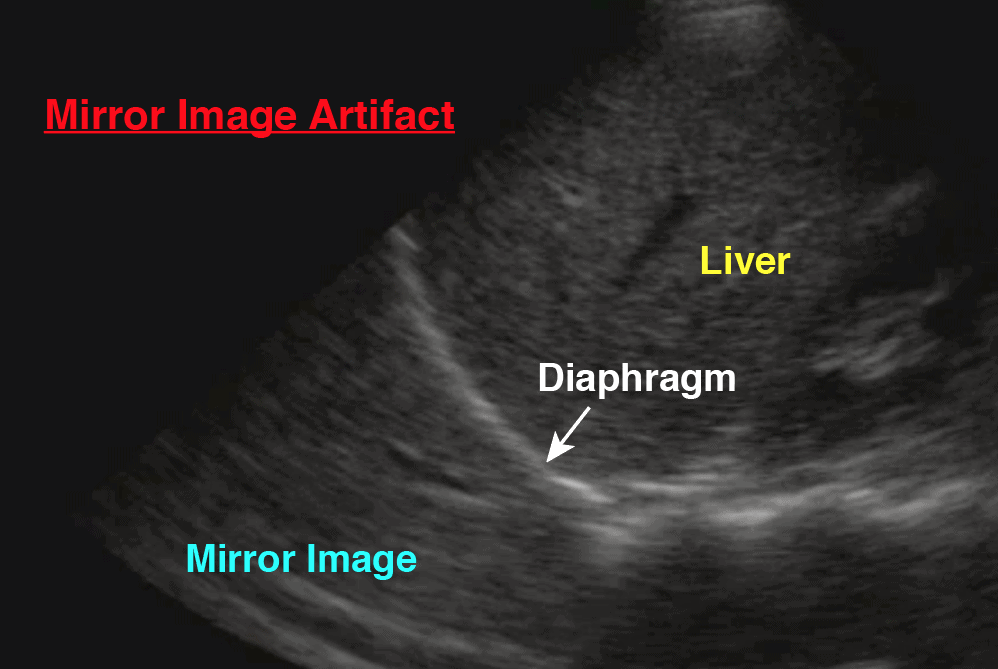

- Always use ultrasound to confirm you’re on the pneumothorax side and confirm you are above the diaphragm and no adhesions or vessels , mark with an X.